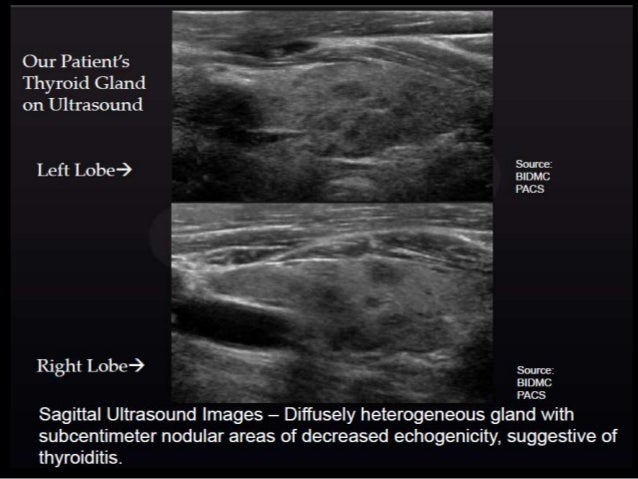

A 52 Year Old Woman With A History Of Hypothyroidism Left Thyroid